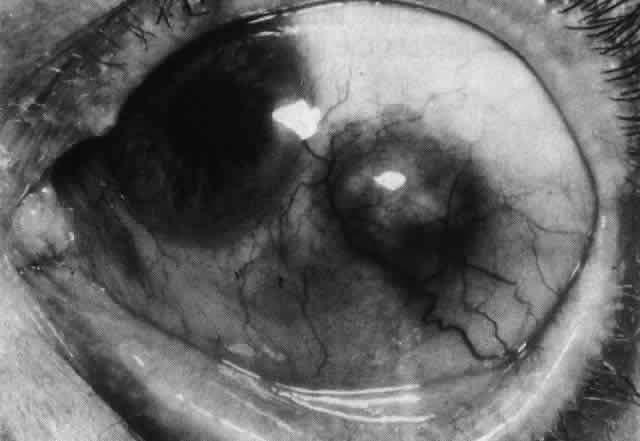

The angiogram is similar to that of diffuse anterior scleritis (i.e., there is a rapid filling pattern and deep scleral leakage of dye).26 Necrotizing Anterior Scleritis with Inflammation Patients with necrotizing anterior scleritis with inflammation not only suffer extremes of discomfort but are in serious danger of losing an eye. Therefore, it is of great importance that the condition be detected early and treated adequately. (It is of equal importance that those varieties of scleral inflammation that are not destructive to the eye should not be treated with drugs that are themselves dangerous.) Accurate diagnosis is the key. Necrotizing scleritis accompanied by inflammation is always painful, waking the patient at night, increasing in intensity day by day, and leading to severe distress. The sclera is swollen, and the overlying inflammation is localized to the center of a lesion or to either end of an extending lesion (Fig. 37; Color Plate 1D). After inflammation, the sclera becomes transparent so that the underlying choroidal pigment becomes visible when viewed in daylight (Fig. 38). These areas may be invisible with the slit lamp. The area of inflammation extends outward around the globe from the original site of inflammation, often joining with other areas of scleritis that have subsequently appeared. If the inflammation is not suppressed, the process will progress around the globe until the whole anterior segment is involved (Fig. 39).

Necrotizing Anterior ScleritisdWithout Adjacent Inflammationd(Scleromalacia Perforans) Necrotizing anterior scleritis without adjacent inflammation appears to be a well-defined condition with little relation in clinical features to necrotizing scleral disease, even though the pathology is similar and the final result is the same. Scleromalacia perforans is characterized by the almost total lack of any symptoms. It occurs almost exclusively in patients with long-standing polyarticular rheumatoid arthritis, the majority of whom are female (Figs. 49 and 50; Color Plate 1E).